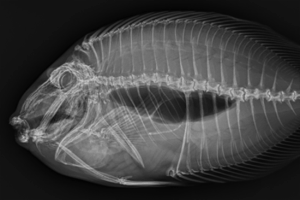

Fish

Fish sometimes receive radiographs too! To begin, they’re gently sedated in anesthetic water and moved quickly but safely to the X-ray table for imaging. Then, they are promptly returned to their anesthetic water for the rest of their exam.

We typically take a right lateral radiograph, meaning the fish’s right side rests flat against the radiology plate. On radiographs, dense structures like bones appear white while air-filled areas, such as the trachea or swim bladder, appear dark, revealing details about the fish’s anatomy and overall health.

We also take dorsoventral radiographs, positioning the fish in a shallow, water-filled trough so the patient remains supported during imaging from above. Capturing these orthogonal, or multiple-view, images allows veterinarians to see the body from different angles, making it easier to identify subtle changes or hidden issues.